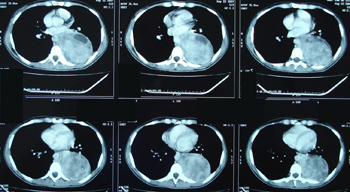

Εικόνα 3 α-δ

Αξονική τομογραφία του θώρακος. Επιβεβαιώνει τα ευρήματα της ακτινογραφίας του θώρακος. Δείχνει μάζα μαλακών μορίων, με νεκρώσεις, στο οπίσθιο μεσοθωράκιο χωρίς σημεία διήθησης παρακείμενων οργάνων.

A-B

Γ-Δ